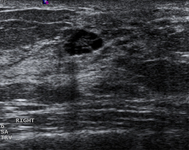

Imagen en ultrasonografía de un fibroadenoma

Cortesía del Dr. Lane Roland, University of Louisville; utilizada con autorización

Ver esta imagen en el contexto de la/s siguiente/s sección/es:

Evaluación de masas en la mama